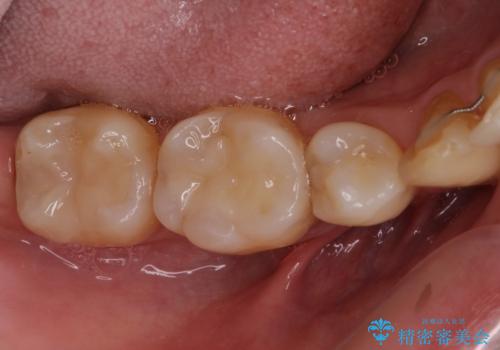

矯正治療後には、下顎臼歯の目立つ銀歯をセラミックインレーにて修復治療を行いました。

口を開けたときに金属が見えなくなり、患者様には大変満足していただきました。